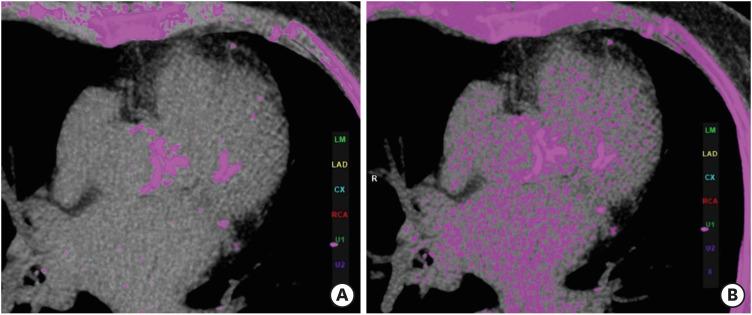

The Coronary Artery Calcium Data and Reporting System (CAC-DRS) is a standardized reporting method for calcium scoring on computed tomography. CAC-DRS is applied on a per-patient basis and represents the total calcium score with the number of vessels involved. There are 4 risk categories ranging from CAC-DRS 0 to CAC-DRS 3. CAC-DRS also provides risk prediction and treatment recommendations for each category. The main strengths of CAC-DRS include a detailed and meaningful representation of CAC, improved communication between physicians, risk stratification, appropriate treatment recommendations, and uniform data collection, which provides a framework for education and research. The major limitations of CAC-DRS include a few missing components, an overly simple visual approach without any standard reference, and treatment recommendations lacking a basis in clinical trials. This consistent yet straightforward method has the potential to systemize CAC scoring in both gated and non-gated scans.

冠状动脉钙化数据与报告系统(CAC-DRS)是一种用于计算机断层扫描中钙化评分的标准化报告方法。CAC-DRS是针对每位患者应用的,代表累及血管数量的总钙化评分。有4个风险类别,范围从CAC-DRS 0到CAC-DRS 3。CAC-DRS还为每个类别提供风险预测和治疗建议。CAC-DRS的主要优势包括对冠状动脉钙化进行详细且有意义的呈现、改善医生之间的沟通、风险分层、恰当的治疗建议以及统一的数据收集,这为教育和研究提供了一个框架。CAC-DRS的主要局限性包括一些缺失的部分、过于简单的视觉方法且没有任何标准参考,以及缺乏临床试验依据的治疗建议。这种一致且直接的方法有可能使门控和非门控扫描中的冠状动脉钙化评分系统化。